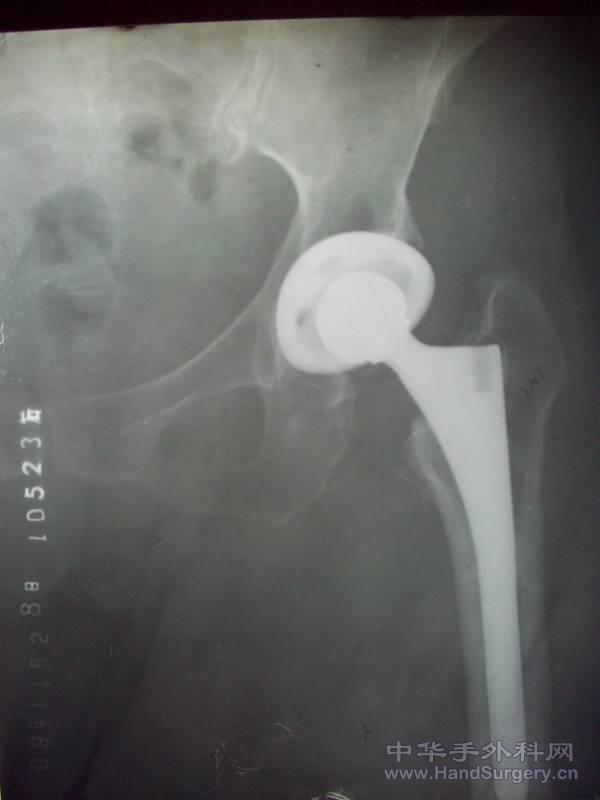

100_1494.JPG 再看张片子,全髋置换。

不完美啊,PFN上面的两针角度有点太斜哎,全髋还可以,看片子股骨颈全截了?

全款置换术后,髋关节功能如何?

功能恢复良好